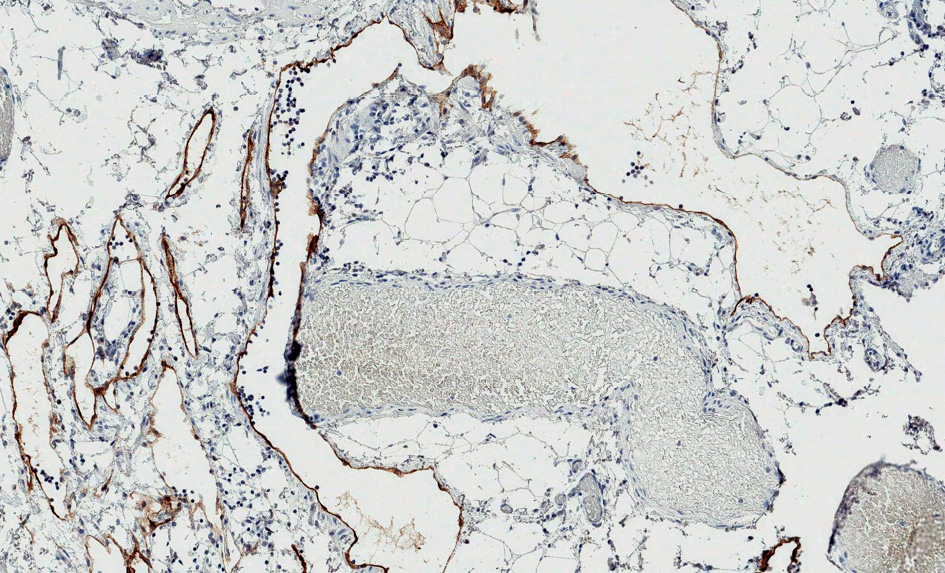

On pathological examination, the macroscopically observed partially opened fatty-fibrous cystic formation 9 cm × 5 cm × 3 cm was identified. Cysts of up to 2 cm filled with whitish, turbid substance were visible. 6 lymph nodes up to 0.5 cm were excised alongside with the lymphangioma. Histologically thin-walled cystic tumor structures were separated by areas of adipose tissue with lymphoid aggregates (Fig. 6). The cavities of the mass were filled with eosinophilic fluid and lymphocytes. The fluid color is similar to milk due to the accumulation of lymphocytes (Fig. 5). Lymphoid aggregates and lymph nodes with histiocytosis were found in the surrounding tissue. Immunohistochemical examination of the lymphatic endothelial marker podoplanin (D2-40) was positive in the endothelial wall of the cystic tumor (Fig. 7). Histological findings support the diagnosis of lymphangioma.